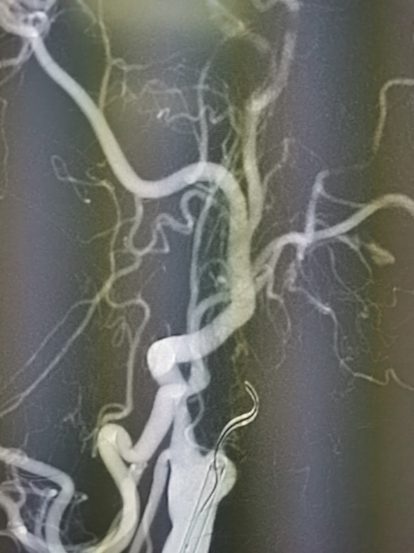

图2 造影见右侧颈内动脉起始处闭塞,闭塞处圆钝,可见自发再通后纤细扭曲血流,返流血较长,可达岩骨段-海绵窦段移行处

图3 通过前交通及后循环软膜支代偿,后交通未见明确开放,代偿情况可